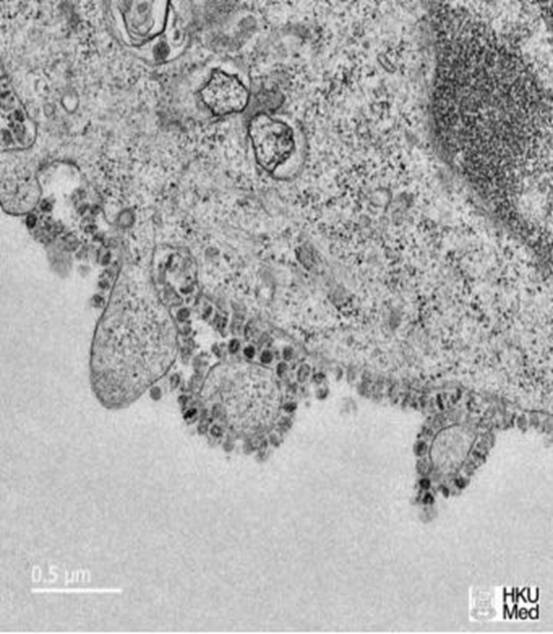

2020年,注定是一個(gè)不平凡的一年,這是個(gè)注定載入史冊(cè)讓人銘記的一年。有人說:“一只蝴蝶輕輕煽動(dòng)翅膀,就可能引發(fā)一場(chǎng)地震或者是海嘯。”然而今天我要說的是或許你不經(jīng)意間的餐桌上一只小小的野味,可能就會(huì)引發(fā)一場(chǎng)沒有硝煙的戰(zhàn)爭(zhēng)(新型冠狀病毒)。這是一場(chǎng)新時(shí)代的、主戰(zhàn)場(chǎng)在中國的“全球性”的戰(zhàn)爭(zhēng)。